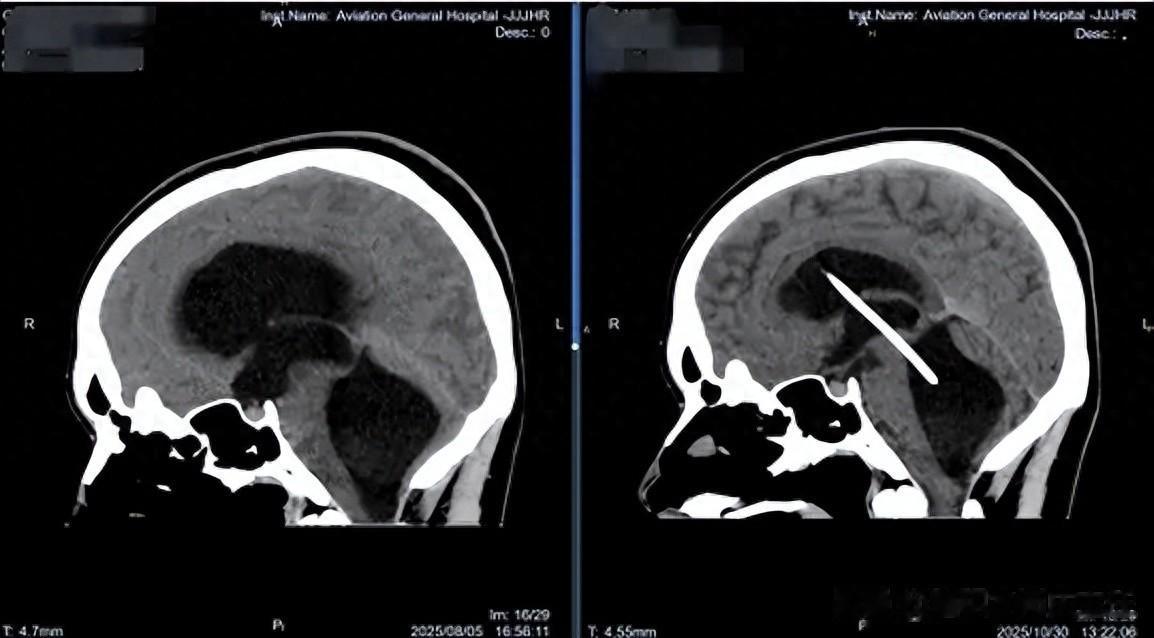

在北京某医院行头颅CT检查后,发现其“脑室系统扩张明显,且第四脑室扩张压迫脑干”。即使静脉用药降颅压,症状也未见改善。到8月5日上午,男孩开始出现“视力下降、视物重影”等危急症状,急性颅内压增高已经压迫视神经。经医生推荐,家人紧急将他送往北京航空总医院,寻求神经外四科肖庆主任的帮助。

影像学检查显示,男孩不仅侧脑室、第三脑室扩张,第四脑室也显著扩张,形成“孤立性第四脑室”样改变。这种情况下,第四脑室内的脑脊液循环受阻,脑干受压,随时可能引发呼吸心跳骤停。且脑脊液检查证实存在“颅内感染”,这很可能是导致分流管失效和脑室粘连的主要原因。